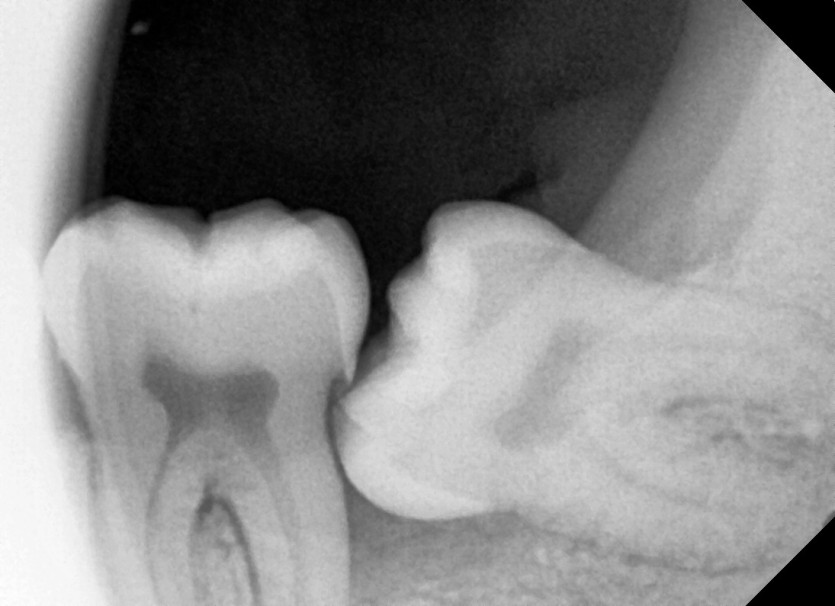

#28,38 사랑니 발치

구강 외과 전문의가 당일 발치했습니다.